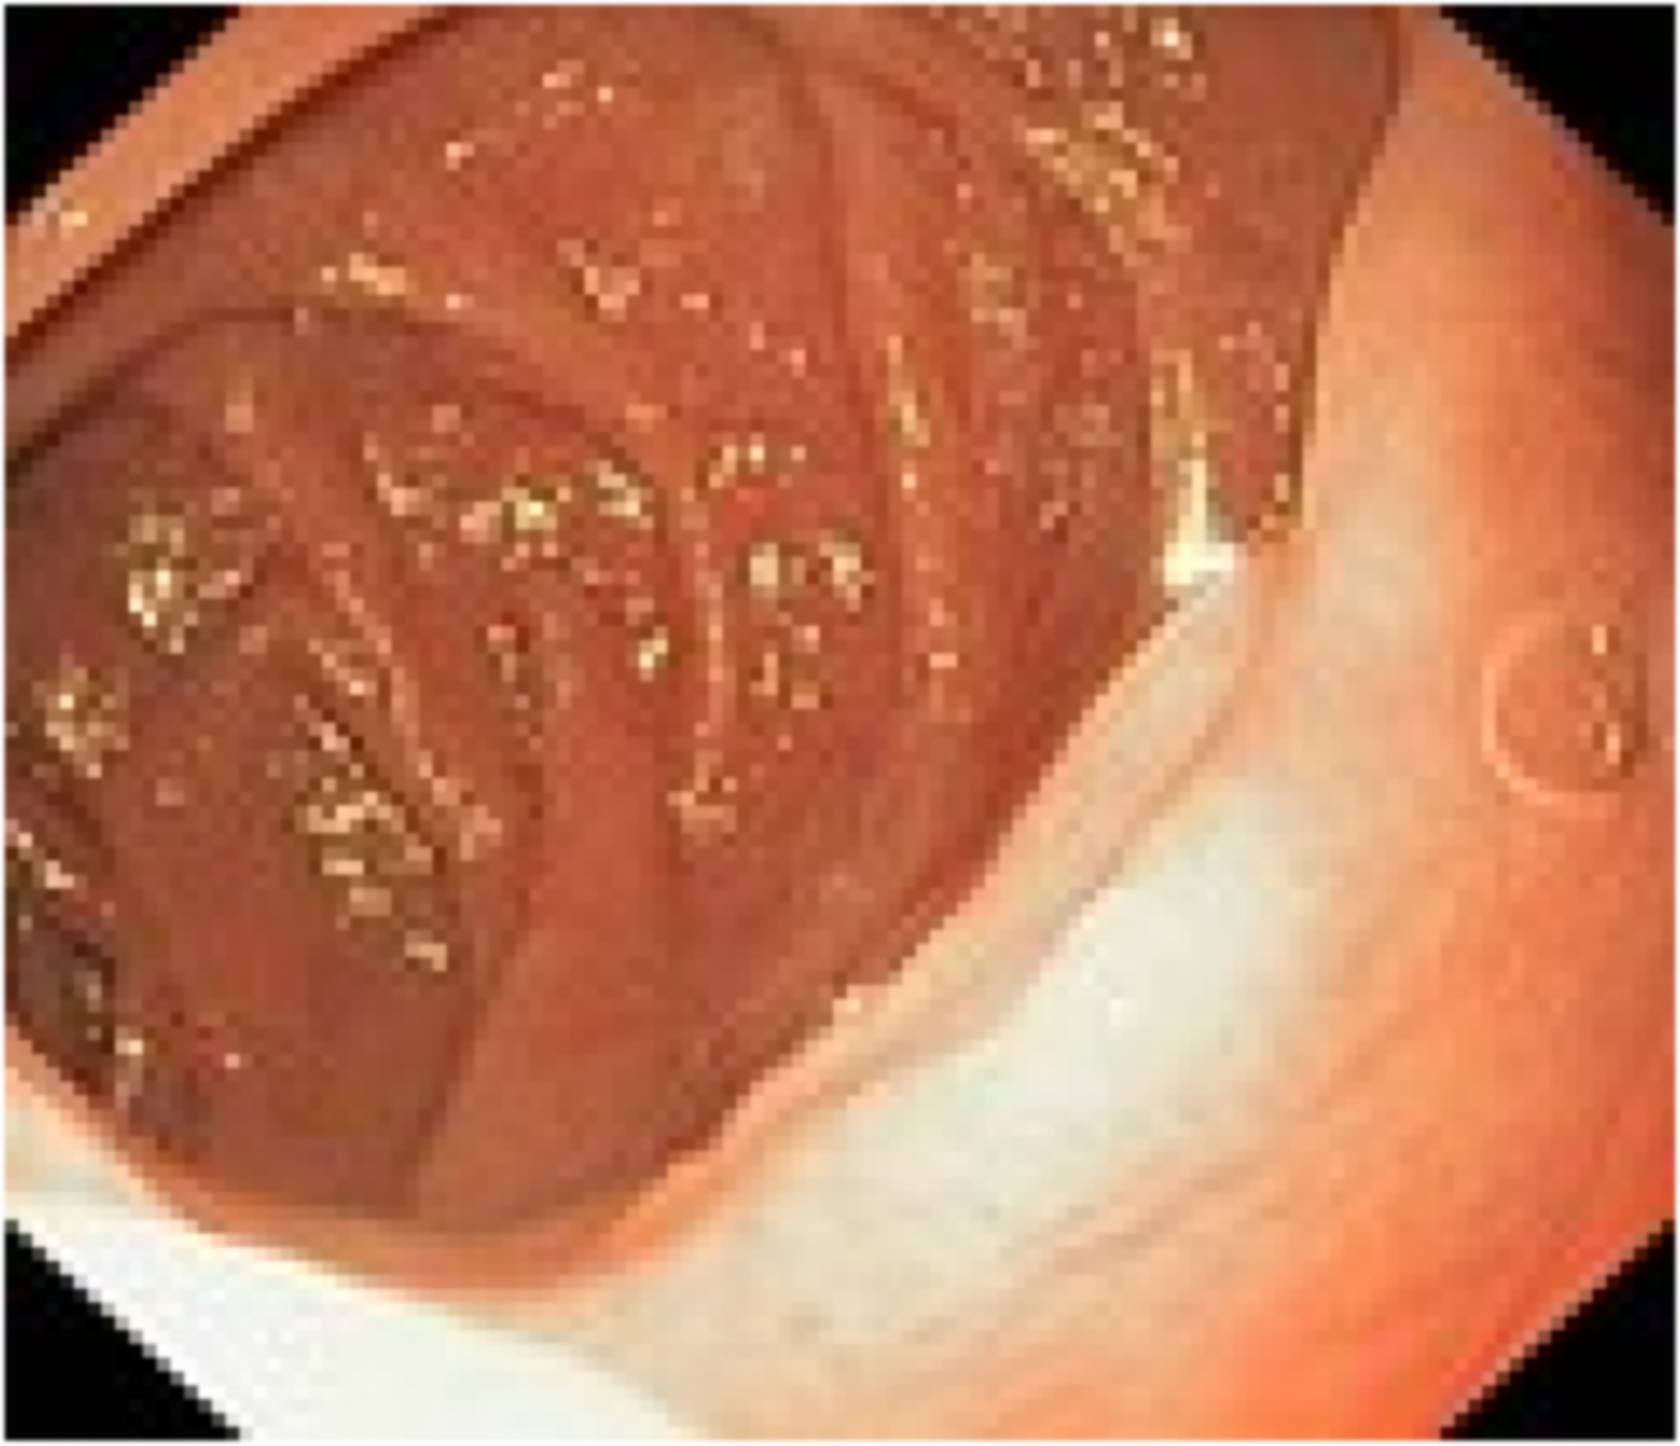

📸✨ Мы рады представить вам результаты улучшения качества нашего эндоскопического оборудования! На фото вы можете увидеть сравнение желудка, снятого на новом и старом аппарате. Разница действительно впечатляет!